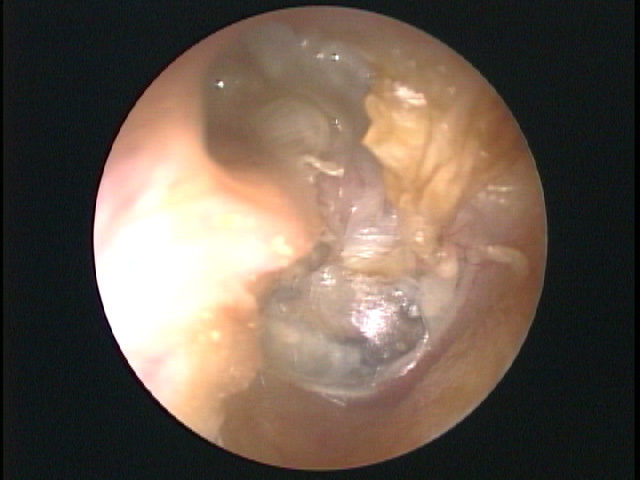

・真珠腫性中耳炎とは、鼓膜の一部が内側(中耳)に陥凹しておきる中耳炎です。

・鼓膜の表面は外耳道の皮膚と連続していますので、角化物(垢)が出ます。

・正常な場合、その垢は皮膚の自浄作用により外側に耳垢として排泄されますが、鼓膜が陥凹するとその内側に角化物が溜まりやすくなります。

・この角化堆積物が、細菌や真菌の培地となり感染、炎症がおこります。この炎症により、周囲の骨を破壊しながら増大するとされています。